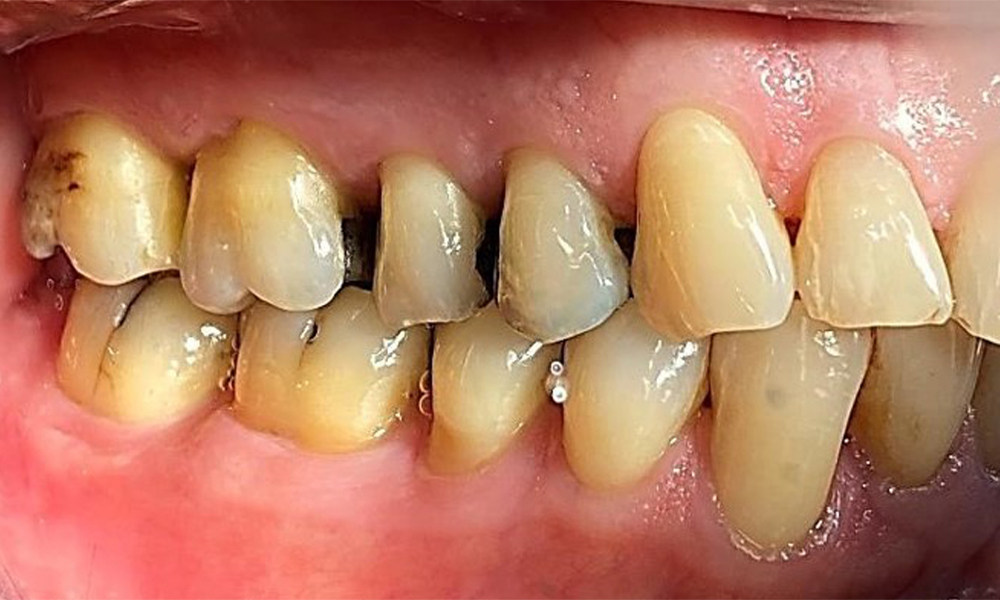

Left lateral view including the recessions.

Fig. 4 Left lateral view including the recessions. © Dr R. Krapf

The patient has a full dentition with 28 teeth, which includes amalgam and composite fillings in the molar and premolar regions. There is a visible clinical marginal gap present on tooth 14. Tooth 27 has an adequate gold inlay. There are also generalized attritions and abrasions. (Fig. 2, Fig. 3, Fig. 4, Fig. 5, Fig. 6)

The patient has stage II, grade B periodontitis (5). At 1 to 3 mm, the clinical probing depths were within the physiological range. Localized probing depths of 5 mm were observed on the mesiopalatal aspects on both 17 and 27. There are generalized recessions of 1–3 mm with partial loss of the interdental papillae (Fig. 2, Fig. 3, Fig. 4)